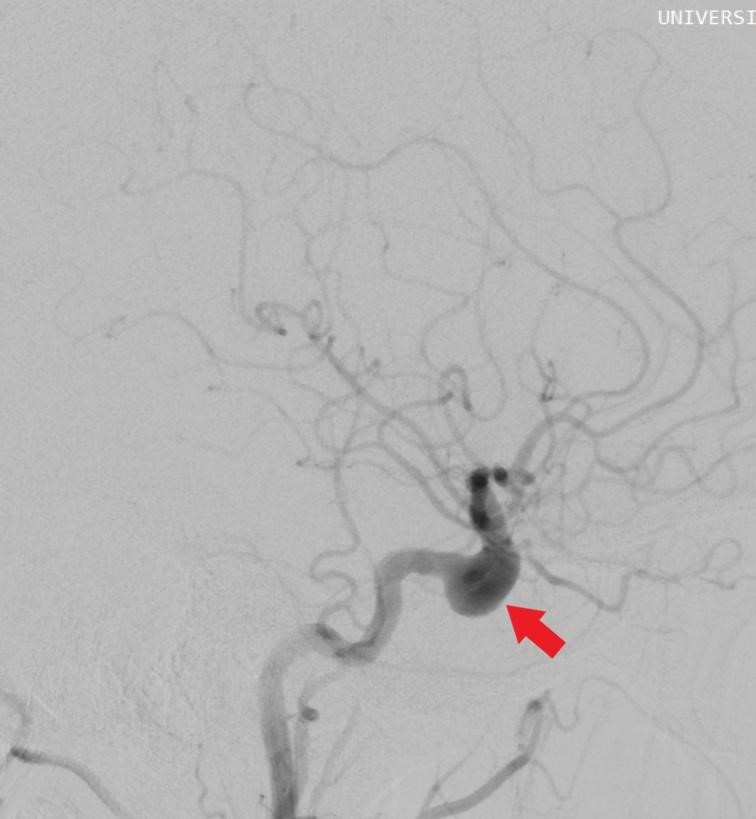

Computed tomography (CT) angiography and magnetic resonance imaging (MRI) were performed, revealing the presence of two aneurysms: a wide-necked aneurysm in the cavernous segment of the right internal carotid artery (ACI) and a small wide-necked aneurysm in the anterior communicating artery (AcomA) (Figures 1-2).

Figure 1: Saccular aneurysm in the cavernous segment of the right ACI.

Figure 2: Wide-necked saccular aneurysm in the cavernous segment of the right ACI.